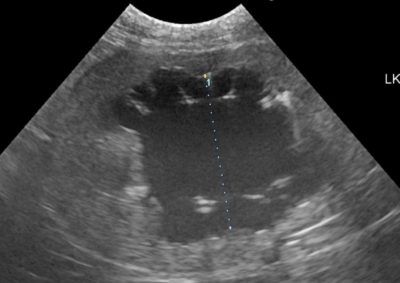

猫の尿管結石に対するSUBシステム(人工尿管設置)